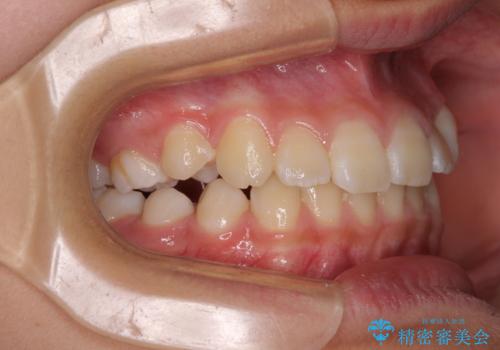

今後残っている乳歯が抜け、永久歯が萌出してくるため、調整可能なリンガルアーチを用いて保定を行っています。

12歳臼歯が萌出するまで経過観察を行い、すべての歯が萌出した後に、全顎矯正治療(Ⅱ期治療)を行っていきます。